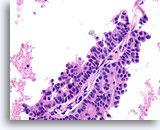

Papillair neoplasma, Borst FNA, Celblok.

Een kleine vergroting van de residuele naaldspoeling van de patiënt in afbeelding 39-42 toont een duidelijk papillaire architectuur. Let op de gelijksoortigheid van de ductale populatie in dit hele veld. Dit monotone patroon duidt meer op een papillair carcinoom dan een papilloom.

40X

Papillair neoplasma, Borst FNA, Celblok.

Een kleine vergroting van de residuele naaldspoeling van de patiënt in afbeelding 39-42 toont een duidelijk papillaire architectuur. Let op de gelijksoortigheid van de ductale populatie in dit hele veld. Dit monotone patroon duidt meer op een papillair carcinoom dan een papilloom.

40X

Papillair carcinoom, Borst FNA, Celblok.

Sterkere vergroting van de patiënt uit afbeelding 39-43 toont een fibrovasculaire kern (open pijl) en een cribriform gebied dat consistent is met een papillair carcinoom (pijl).

10X

Papillair carcinoom, Borst FNA, Celblok.

Sterkere vergroting van de patiënt uit afbeelding 39-43 toont een fibrovasculaire kern (open pijl) en een cribriform gebied dat consistent is met een papillair carcinoom (pijl).

10X